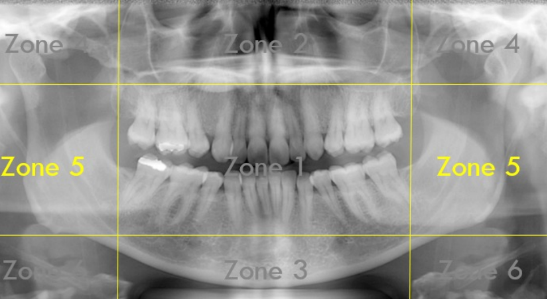

What Zone Is This?

Zone 5: Spine and Ramus

What do we see in Zone 5?